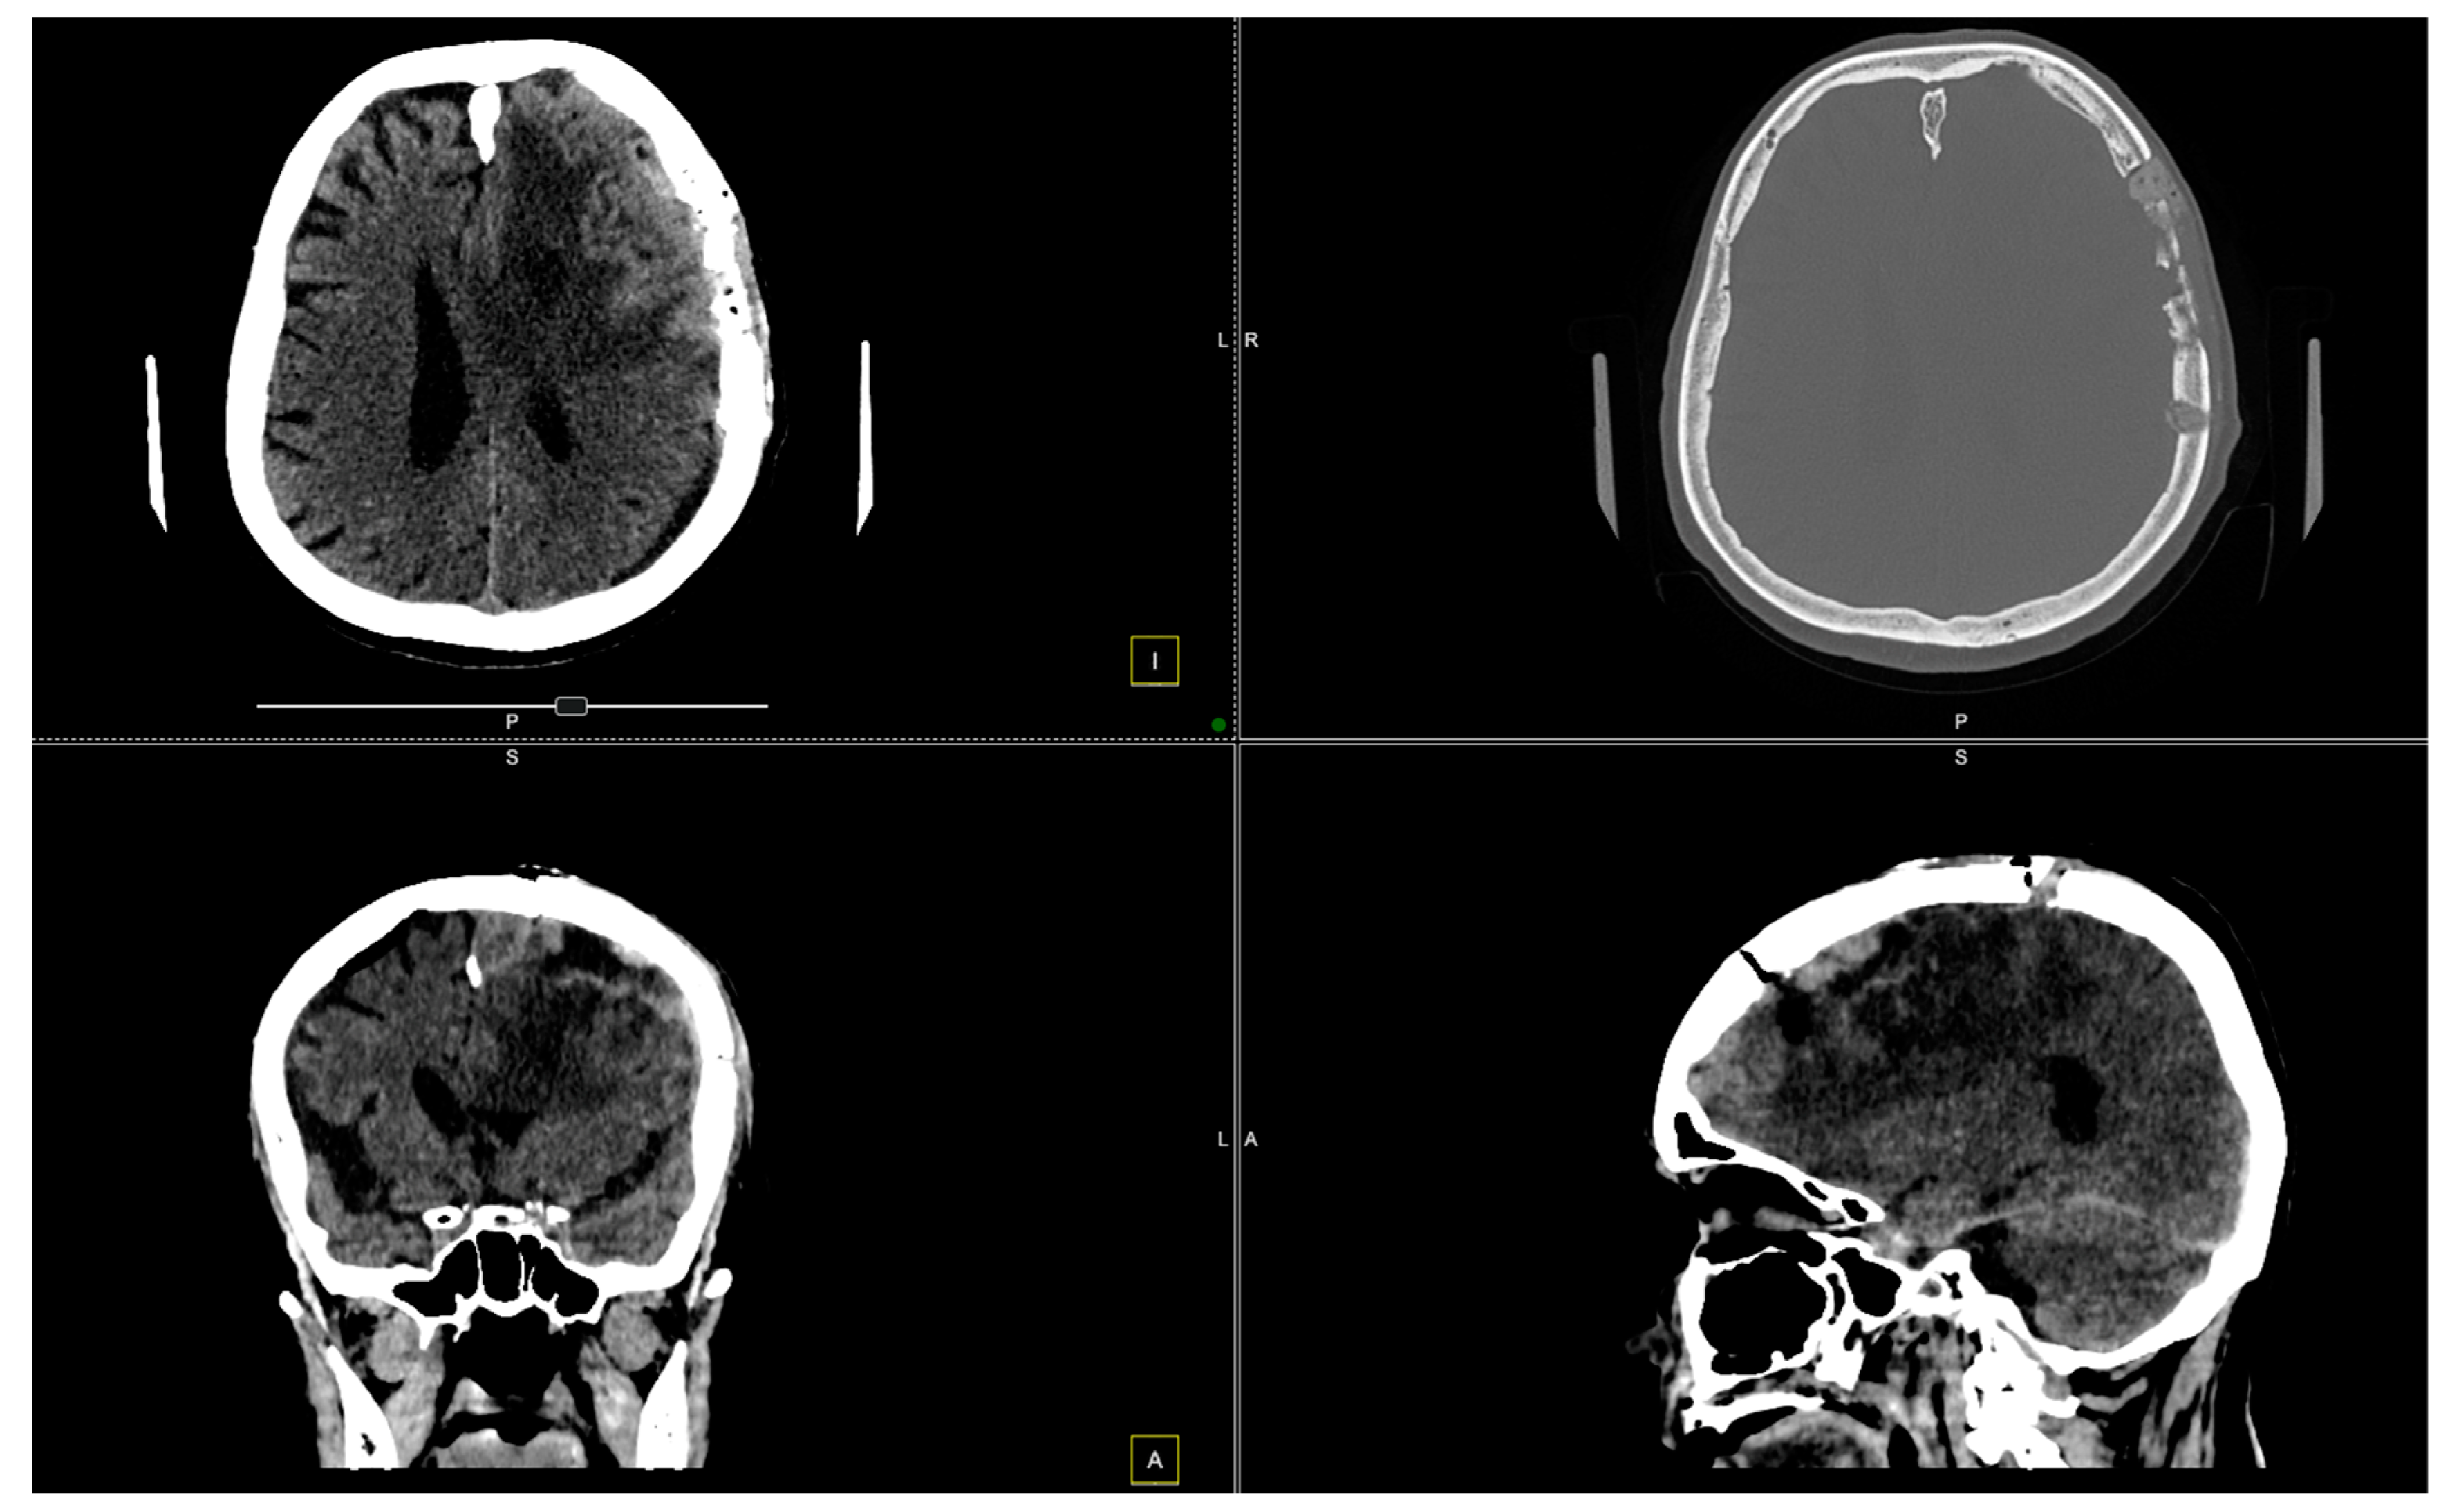

2. Case Presentation